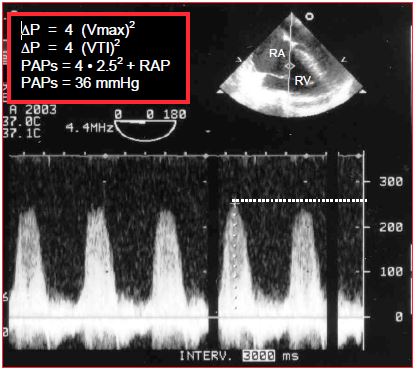

In echocardiography, the Doppler beam is aligned with the TI jet and the computer automatically performs the calculation (Figure 15.7).

Figure 15.7: Echocardiographic calculation of systolic pulmonary pressure by the velocity of tricuspid insufficiency (TI). In the top right illustration, the Doppler beam is aligned with the TI jet through the tricuspid valve. The spectral display provides the maximum TI velocity, which in this case is 2.5 m/s. A simplified Bernoulli equation (ΔP = 4 V2) is used to calculate the prevailing pressure gradient (ΔP) between the RV and RA during systole by measuring the maximum velocity (V) of the TI. RA pressure (in this case 10 mmHg) must be added to this result (4 x 2.52 = 26 mmHg) to determine the pressure value in the RV during systole. In the absence of pulmonary stenosis or a VSD, this pressure is equal to systolic pulmonary arterial pressure (PAPsyst).

ΔP   =   4 (Vmax)2

where ΔP is the pressure gradient between the RV and RA during systole, and Vmax the maximum TI velocity.

PAPsyst = 4 (Vmax TI)2 + RAP